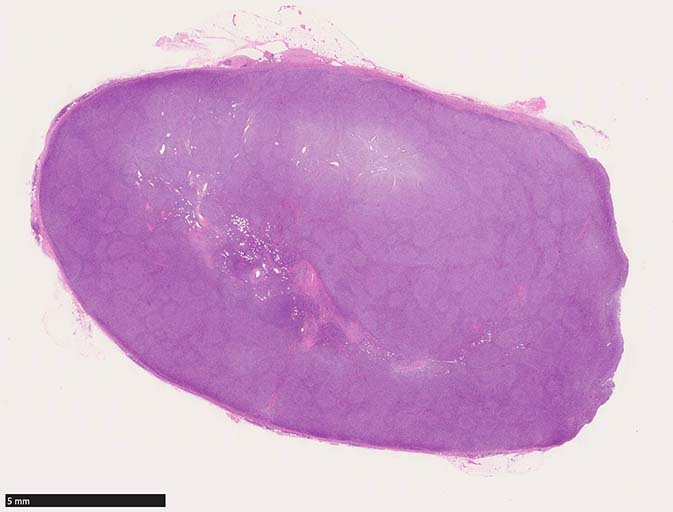

鼠径リンパ節病理標本(初発時リンパ節標本)

鼠径リンパ節生検組織では, びまん性に中~大型のcentroblasticまたはimmunoblastic cellsが密に増殖しCD21染色を行っても明らかな濾胞形成は認められない.

diffuse patternの増殖を示すリンパ腫病変と考える.